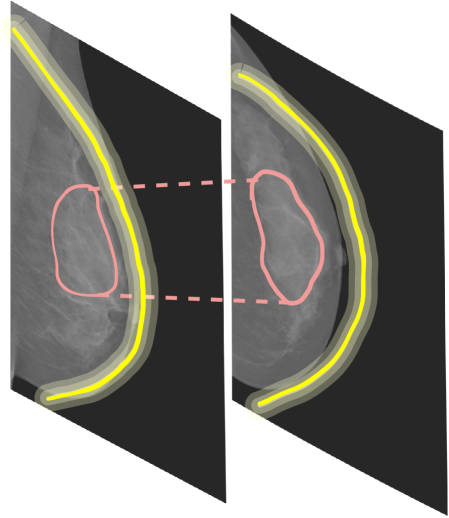

Refer to caption

Figure 2: Example of a mammography exam. Images are from the CBIS-DDSM dataset and present an exam with four views: left CC (L-CC), right CC (R-CC), left MLO (L-MLO), and right MLO (R-MLO). Horizontal couples are bilateral views (blue), while vertical couples are ipsilateral views (red). Arrows indicate the relations among views. Bilateral relations reveal an asymmetry (as there is a mass on the left that is not present on the right). Ipsilateral relations give a better view of the specific mass.

Among the several imaging modalities, mammography is considered the best method for breast cancer screening and the most effective for early detection [3]. A mammography exam comprises four X-ray images produced by the recording of two views for each breast. The CC view is a top to bottom view, while the MLO view is a side view. During the reading of a mammography exam, employing multiple views is crucial in order to make an accurate diagnosis, as they contain complementary information. Admittedly, comparing ipsilateral views (CC and MLO views of the same breast) helps to detect eventual tumors and helps to analyze the 3D structure of masses [5]. Whereas, studying bilateral views (same view of both breasts) helps to locate masses as asymmetries between them are an indicating factor [5]. An example of a complete mammogram exam with ipsilateral and bilateral views is shown in Fig. 2.